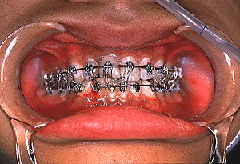

ギブスの替わりに、歯に針金をつけてこうやると、ちゃんと、元の噛み合わせになりましたね。

約一カ月でちゃんと骨はくっ付きます。

この方法は、手術無しで治しましたが、顎関節など、骨折の部位によっては、手術をする場合もあります。